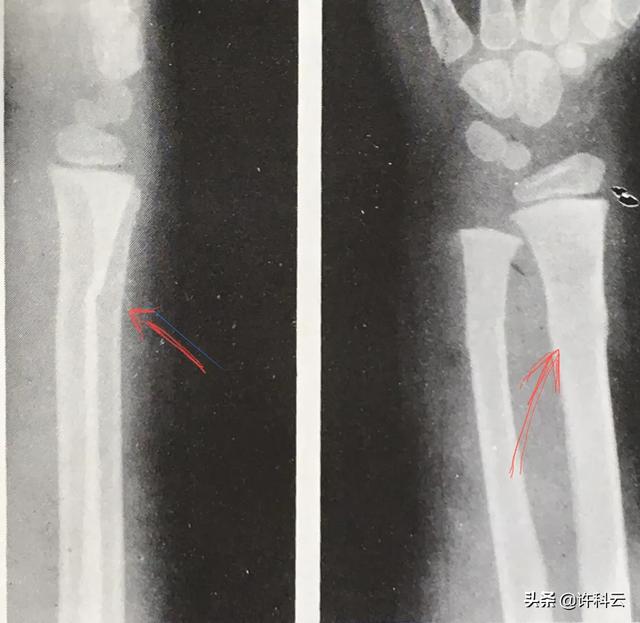

1⃣️你这个问题要以人家在其它医院检查的新骨折为依据,可无条件依据医院的X光片检查结果与派出所商谈有关医药费及误工补贴等事宜!⬇️红箭头处为儿童青技骨折,从桡骨远段骨皮边缘不整齐可诊断、

2⃣️为什么一医院查不出骨折?因为在没有足够的暴力致骨折发生错位时,是一两个角度拍片查不出骨皮质中断分离的,在X线投照的角度上,因为中心线没有从骨折缝中穿过,就象五个指头并拢侧面看只有一个手指样,只有从多个角度才能发现骨皮质有中断,这要靠医生有临床经验,在认定病人主诉某部位有疼痛及功能障碍时,如在后胸肋上因内出血就有呼吸疼痛症状,要拍几个角度,还是能查到轻微骨折的。⬇️人的胸肋象桶状,从锁中线向心口为肋软骨,呼吸运动弹性大,钙质少,产生压迫骨折多在腋下及后肋,前肋小暴力不容易产生骨折、

3⃣️轻微骨折在两周内因消肿散淤后开始产生棉絮状骨痂,就容易在骨折线外明显看到骨皮质断裂。我也曾碰到一例病人几月前自己受伤接着又与人纠纷,并在县医院诊断为骨折,想讹诈对方,可对方心中有数,并没有打他,我凭经验断定:你那是旧伤,已形成骨痂了,新伤怎能有这个表现,一场纠纷终于摆平了。⬇️你看到下方胸片中的条影多为后肋影,前肋很难显出!凡四肢上有骨裂而误诊的多是在投照角度没有对准到骨裂隙中心造成的。